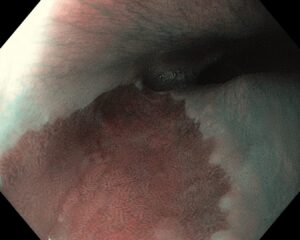

Атлас

В эндоскопическом атласе обычно представлены изображения и видео, полученные во время процедур, проводимых врачами-эндоскопистами. Эти изображения и видео могут использоваться для обучения студентов медицинских учебных заведений, повышения квалификации медицинских работников, а также для консультации врачей при диагностике и лечении различных заболеваний.